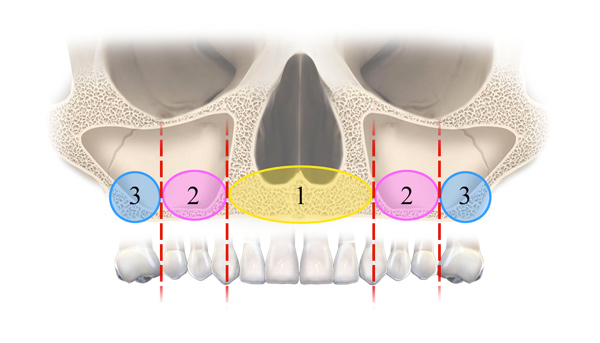

Radiographic evaluation of the edentulous maxilla is necessary for determining whether axial, tilted, or zygomatic implants would be indicated to establish optimal posterior support with proper anterior-posterior distribution of implants for a fixed prosthesis. Because the edentulous maxilla is divided into three radiographic zones, a systematic assessment of the residual alveolar bone available for implant placement can be made. In this pretreatment screening protocol, the alveolar bone supporting the maxillary anterior teeth is designated as zone 1, while the premolar region is considered zone 2 and the molar region zone 3 (Figure 4). Analysis of the radiographic results according to this scheme can enable the surgical and restorative team to devise a preliminary treatment plan. In complex situations, 3-dimensional (3D) radiographic evaluation may still be necessary to confirm the preliminary conclusions.

Evaluation of the various zones of the maxilla will guide the surgical team in determining the type of surgical approach to take for placement of implants. Use of panoramic scout film as well as 3D radiography to evaluate the zones will help the surgeon understand the quantity of bone available for each intended implant site.

Fig 4. The zones of the maxilla.

Figure 4